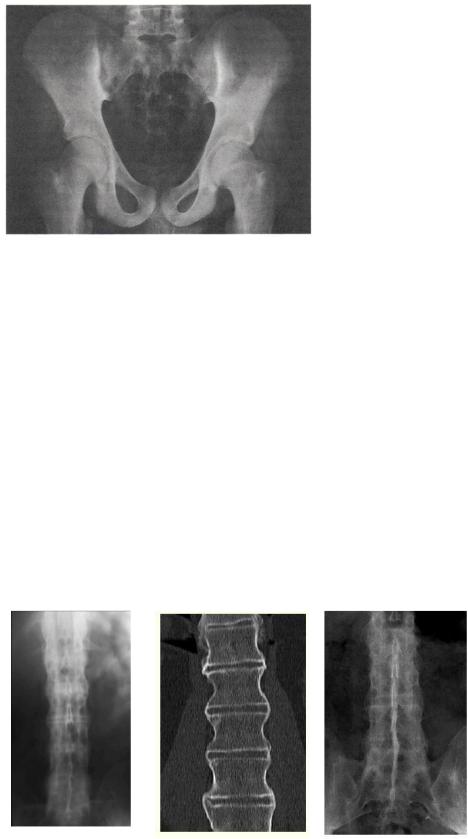

Поскольку первые изменения всегда формируются в области крестцово-подвздошных сочленений, в случае подозрения на АС в обяза - тельном порядке выполняют рентгенограмму таза в передне-задней проекции, захватывающую все кости таза и тазобедренные суставы. Ранний признак сакроилеита — сочетание участков расширения суставной щели за счѐт эрозий на фоне распространѐнного субхондрального

остеосклероза, сначала со стороны подвздошной кости, а затем и со стороны крестца. Очаговое, а затем полное анкилозирование крестцово - подвздошных сочленений, а также сужение щелей этих су ставов — поздние признаки сакроилеита (рис. 6-6).

Рис. 6-6. Двусторонний сакроилеитIIIст. (по Келлгрену).

В первые годы сакроилеит может быть односторонним и несимме - тричным, но в дальнейшем обычно отмечают двусторонние и симме - тричные изменения.Изменения в позвоночнике обычно выявляются через несколько месяцев или лет от начала болезни.

К числу поздних изменений относят синдесмофиты: линейные зоны оссификации наружных частей фиброзных дисков, в основном не выходящие за контур тел позвонков (первые синдесмофиты обычно появляются на границе поясничного и грудного отделов), окостенение межостистых и жѐлтых связок, атакже анкилоз дугоотростчатых суставов с оссификацией их капсул. Распространѐнная оссификация указанных структур создаѐт картину «бамбуковой палки» (рис.6-7).

Рис. 6-7. «Бамбуковый» позвоночник.